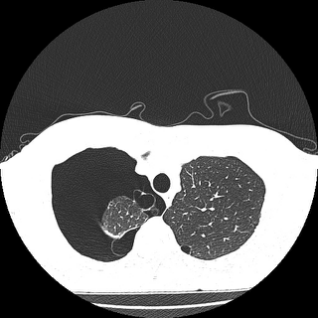

随后,男子被转入龙岗区人民医院急诊科,再转入了心胸外科就诊,做了胸部CT后发现——

双肺可见多发肺大疱

右肺破裂引起气胸

右肺组织被压缩了75%